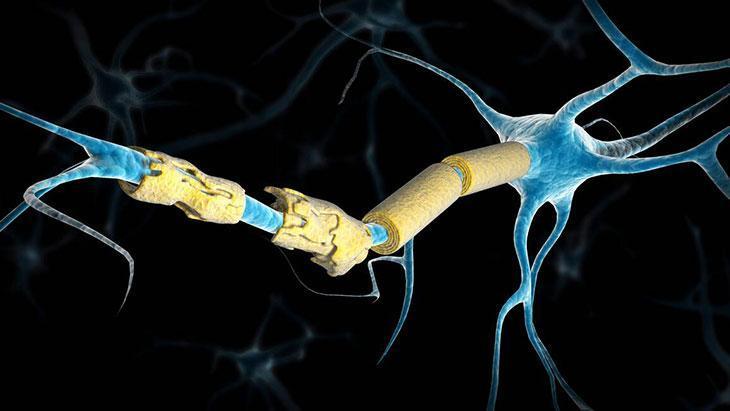

Öncelikle şunu belirtmek gerekir ki bu hastalığa "multipl" denmesinin nedeni, beyin ve omuriliğin birçok farklı alanını etkilemesindendir. Aniden ortaya çıkabilir ya da kaybolabilir. Belirtileri çok çeşitlidir. Hastadan hastaya değişiklik gösterebileceği gibi aynı hastada da zaman içinde farklılaşabilir.

"Skleroz" denmesinin nedeni ise hastalığın beyin ve omuriliğin hasarlı alanlarında sklerozan plaklar yani sertleşmiş dokular oluşturmasıdır. Özetle MS, merkezi sinir sistemini oluşturan beyin ve omurilik üzerinde yıkıcı etkileri olan, kişinin yaşamsal fonksiyonlarını bozan ve ataklarla seyreden bir hastalıktır.

MS, vücudun bağışıklık sistemindeki normal işleyişi bozar. Bilindiği gibi normal şartlarda bağışıklık sistemi bizi hastalıklara karşı korur. Değişik nedenlerle bazen bu sistem vücuttaki normal dokuları da yabancı görmeye başlar ve onlara hücum eder.